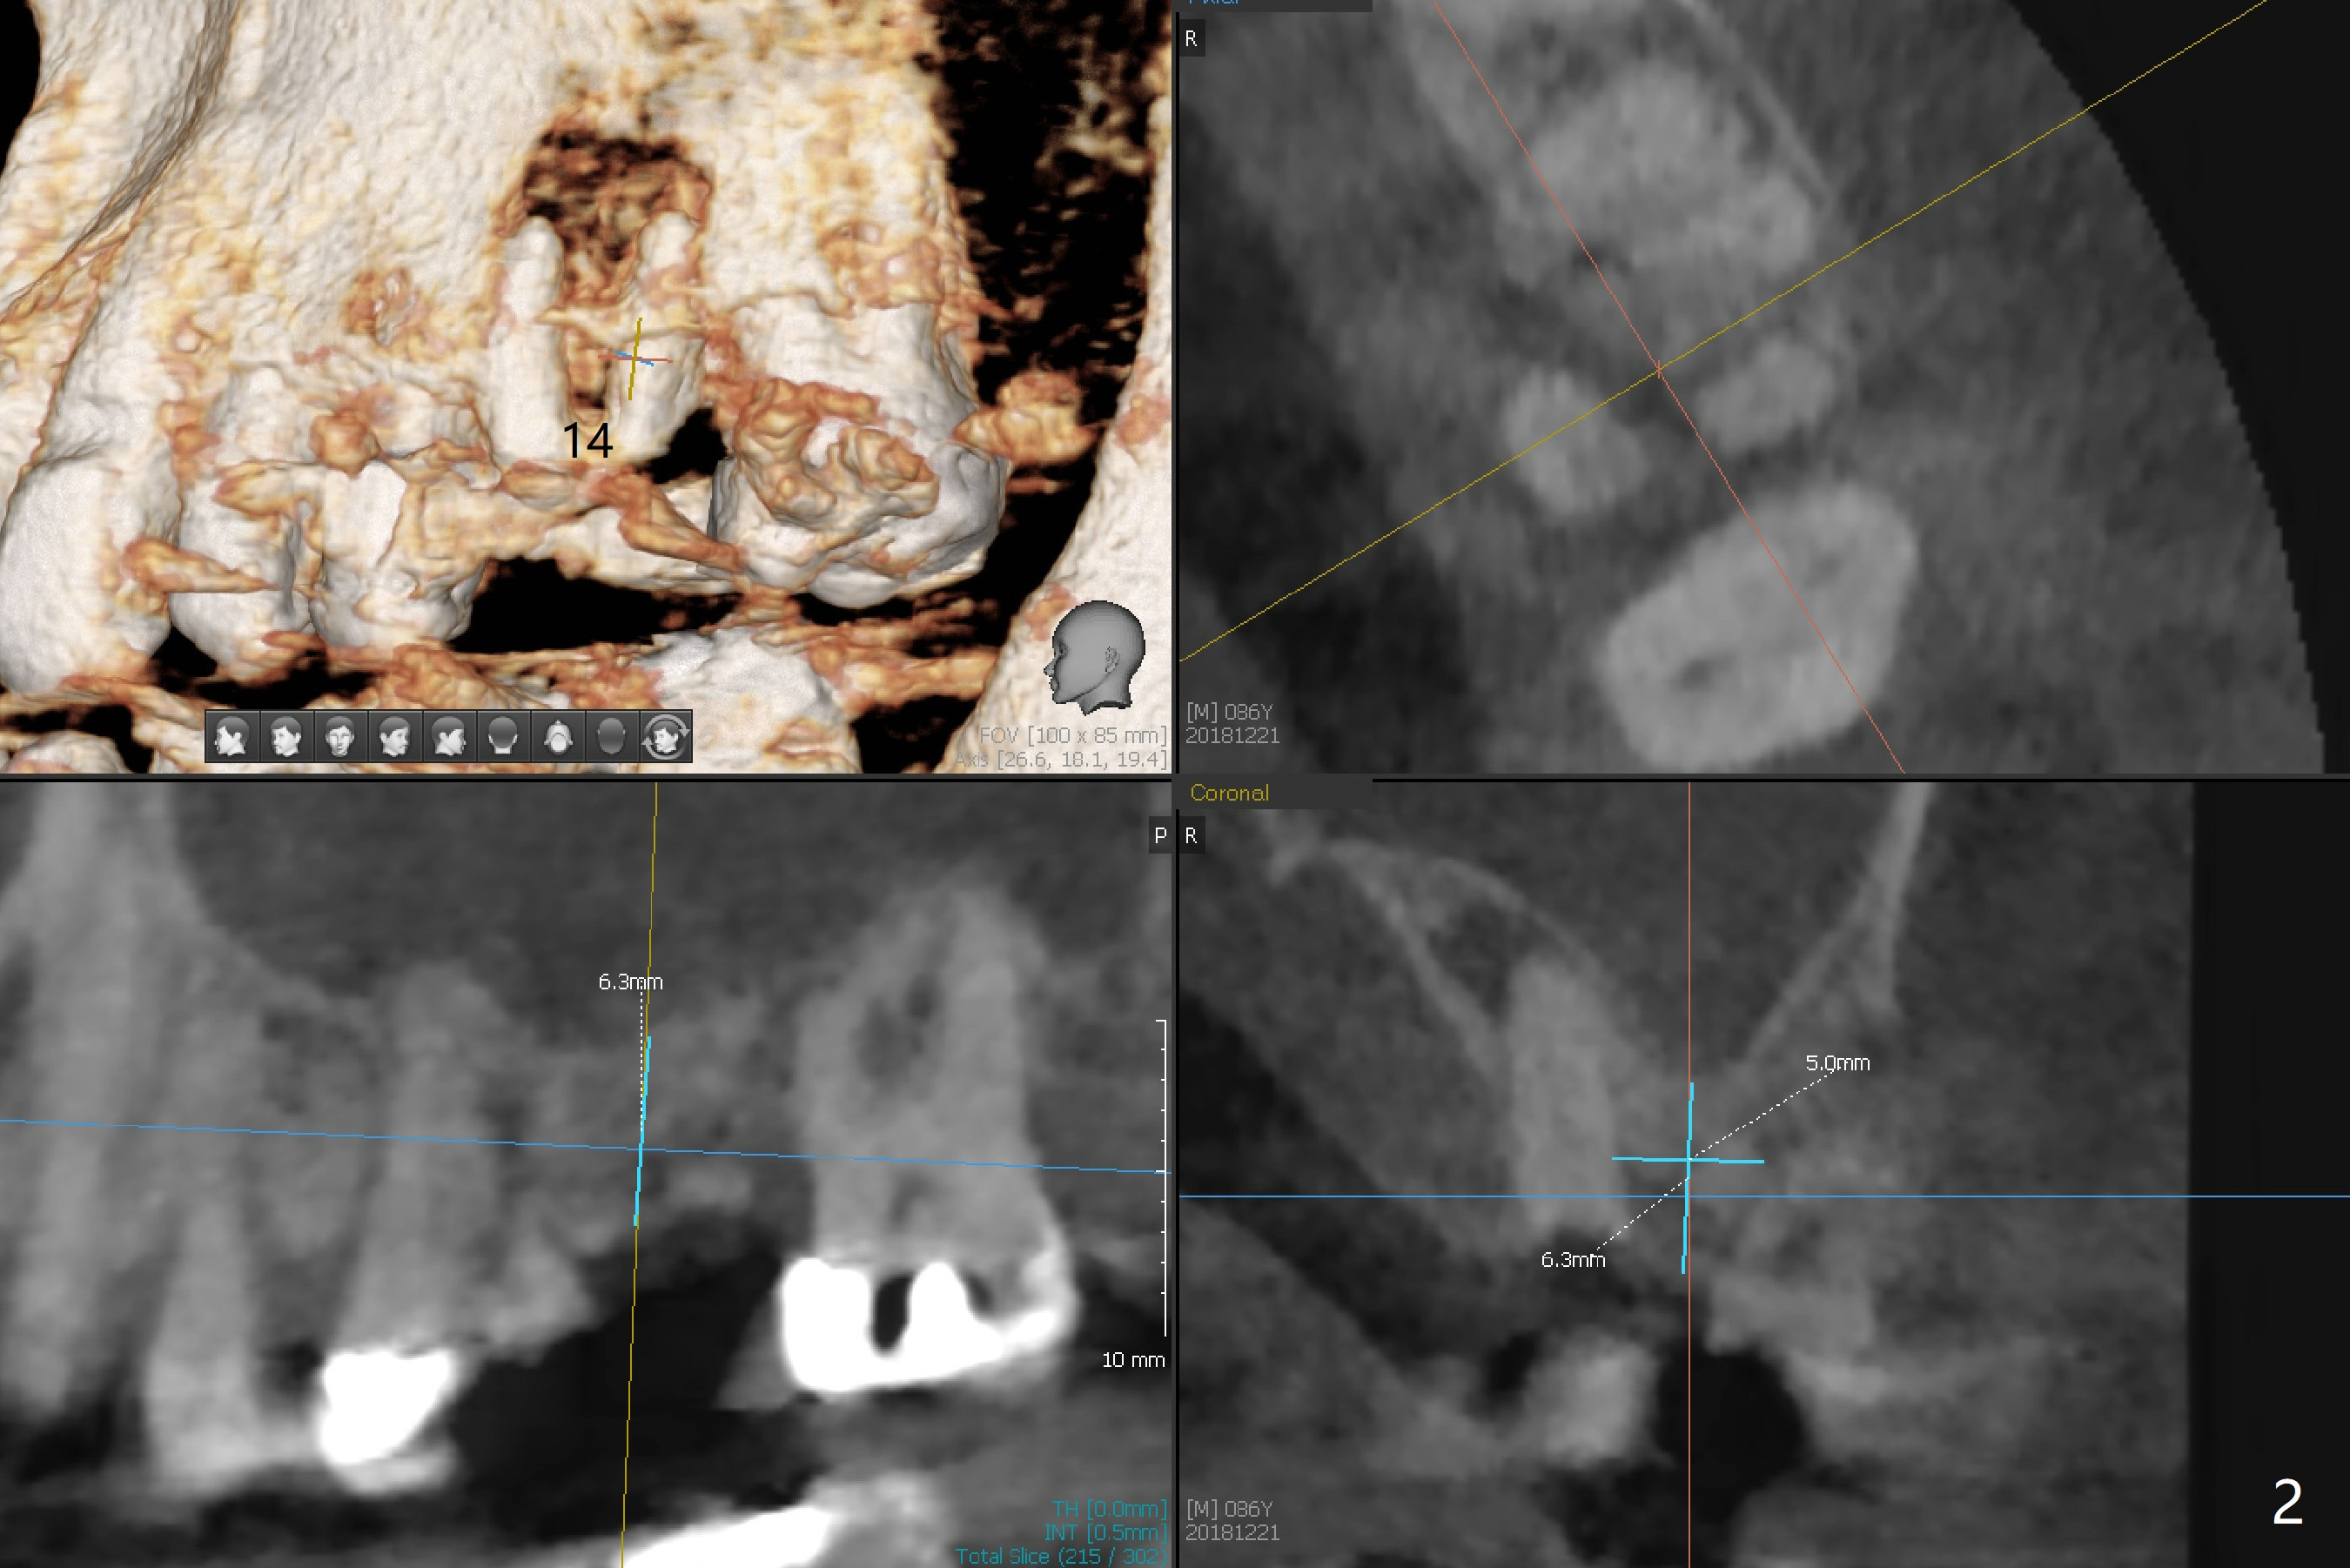

A 86-year-old man presents to clinic with chief complaint of irritating chipped tooth lower right (Fig.1 #31). Composite is placed on the condition that he should return for #14 residual root treatment (Fig.2). Since there is large periapical radiolucency and short bone height (~6 mm), should the tooth be extracted for immediate sinus lift and delayed implant or immediate implant (Fig.3)?